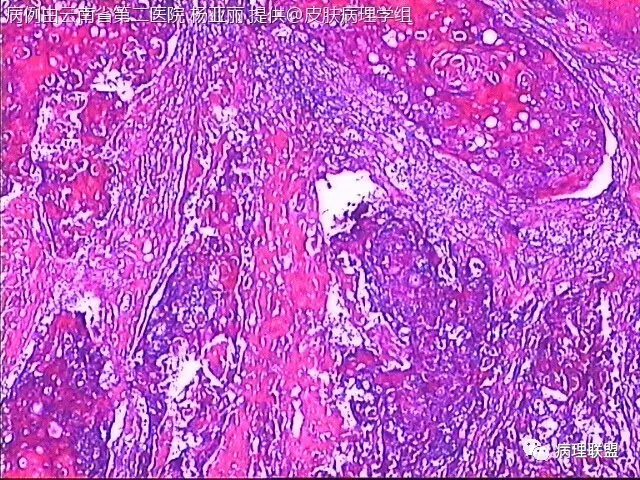

M/53 左手食指包块(皮肤鳞癌VS转移性鳞癌)

请各位老师帮忙看看,男性,53岁,左手食指包块 (病例由云南省第二医院 杨亚丽 提供,致谢!)

鳞癌没有问题。问题是否是转移癌:有否与表皮相连,病史演变如何?

@邓永键 谢谢邓主任,据说病人鼻子上有肿瘤才来切的手上的小包块,右手有,左手也有三四个,等我再问问鼻子上的是什么。看着细胞异型不明显,生长方式倒是确实不好。第6图有和表皮的关系,不相连,邓老师,鼻子上的肿瘤确实是鳞癌,这么说来手上的是转移的就很合理了。邓主任真是高,佩服!